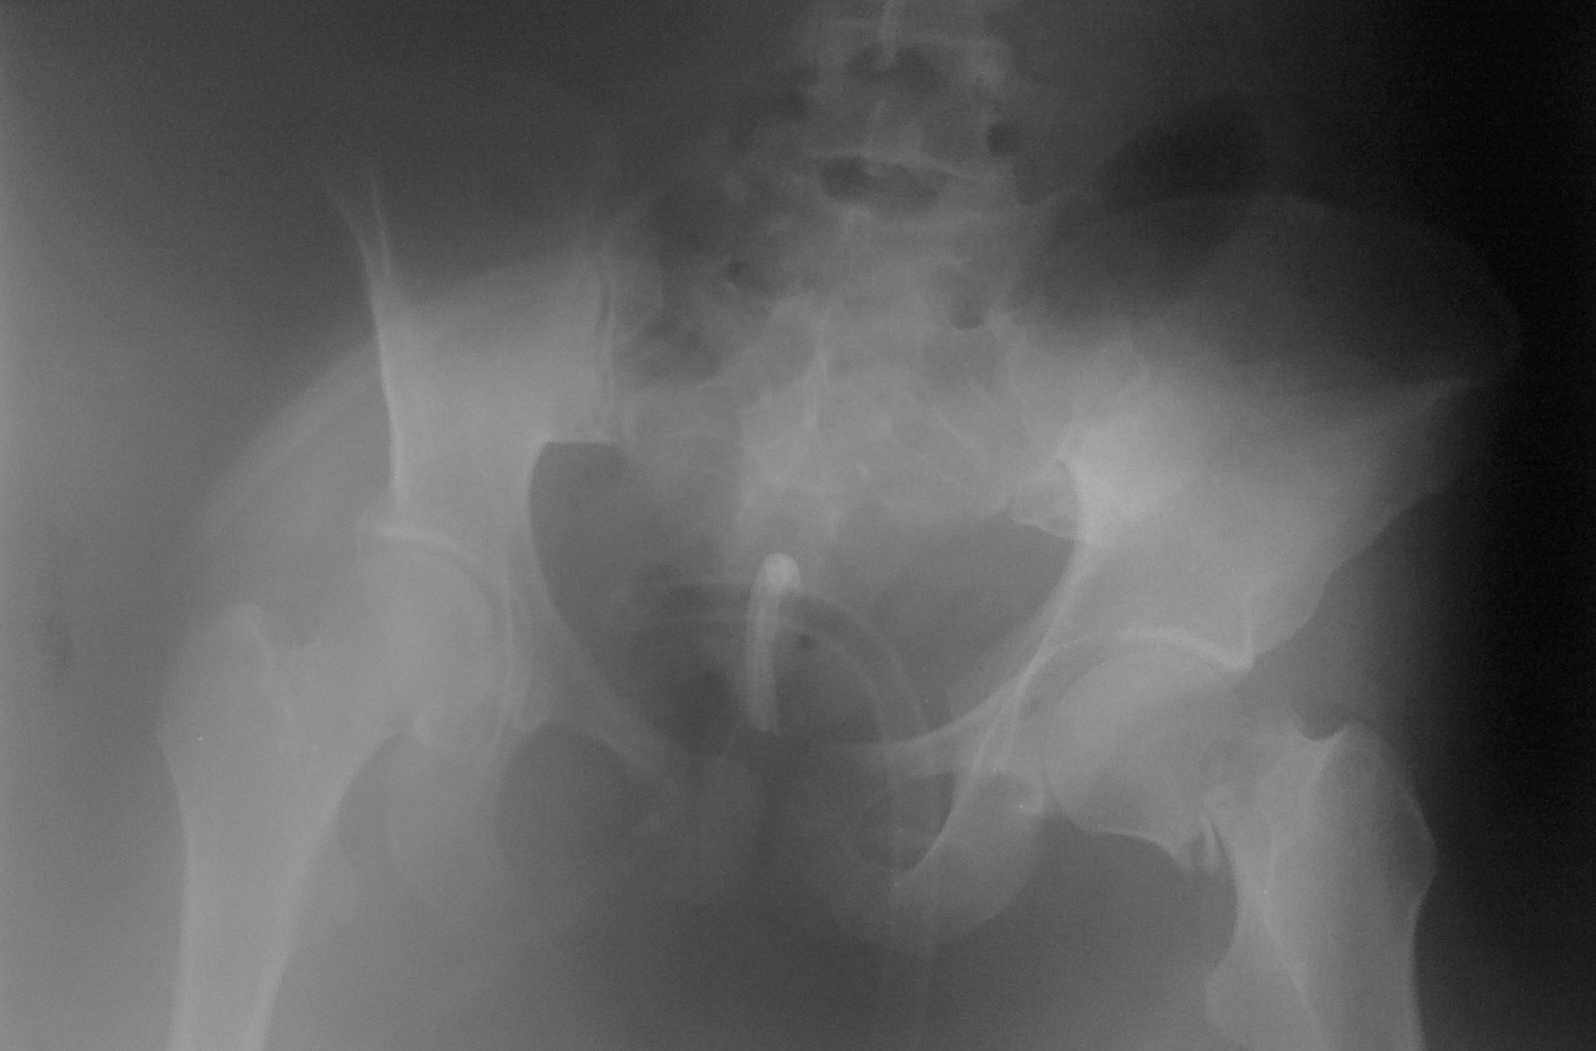

Больная М 19 лет поступила в приемное отделение 20.04.10г. в 21:35. Диагноз: тупая травма живота. Разроыв селезенки. Разрыв печени. Внебрюшинный разрыв ммочевого пузыря. паравезикальная гематома. Внутрибрюшное кровотечение. Забрюшинная гематома. Травматический шок. Выпоглнена лапаротомия. Спленэктомия. Ушиван6ие разрывов правой доли печени. Ушивание внебрюшинного разрыва мочевого пузыря. Ревизия органов брюшной полости. Цистостомия. Дренирование паравезикального пространства. Санация дренирование брюшной полости. дренирование плевральной полости слева.В настоящее время больная в сознании, контактна, на вопросы отвечает.

У больной перелом крыла левой подвздошной кости в зоне крестцово-подвздошного сочленения. перелом лонной кости и седалищной кости справа сог смещением отломков. Закрытый перелом шейки левой бедренной кости.Планируется выполнить сиабилизацию аппаратом нижней фиксации.Вопрос: стабилизация костей таза? как лучше выполнить? подскажите пожалуйста.

Очень похоже по снимку, что еще есть трансфораминальный перелом крестца справа. Без КТ тяжеловато, конечно.

Для адекватного предоперационного планирования и решения вопроса о выборе фиксатора необходимо выполнить компьютерную томографию, или в её отсутствие Ро-укладку inlet. Так как, судя по рентгенограмме имеется многофрагментарное повреждение крыла, что может потребовать изменения тактических подходов к лечению.